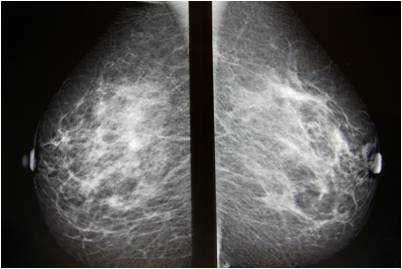

Mammografia

Strumento diagnostico per anomalie al seno. Raccomandata ogni due anni per donne senza storia oncologica, annualmente per chi ha storia familiare.